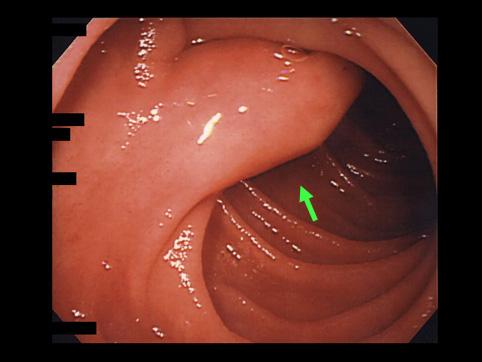

A case of duodenal Brunner's gland hyperplastic polyp which was removed by an endoscopic polypectomy.

종양양 병변/과형성 용종

십이지장/하행각

0형(표재형)/I형(Ip)

15~19